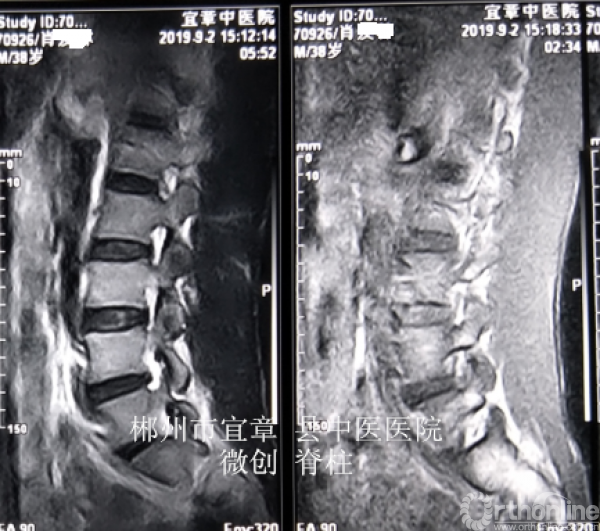

病程:腰痛伴左下肢放射痛5年,加重5天入院,入院诊断:L4/5椎间盘脱出伴坐骨神经痛。

MRI、CT影像学表现:

术后复查MRI示突出物已经取出,患者感觉效果杠杠滴,很满意。